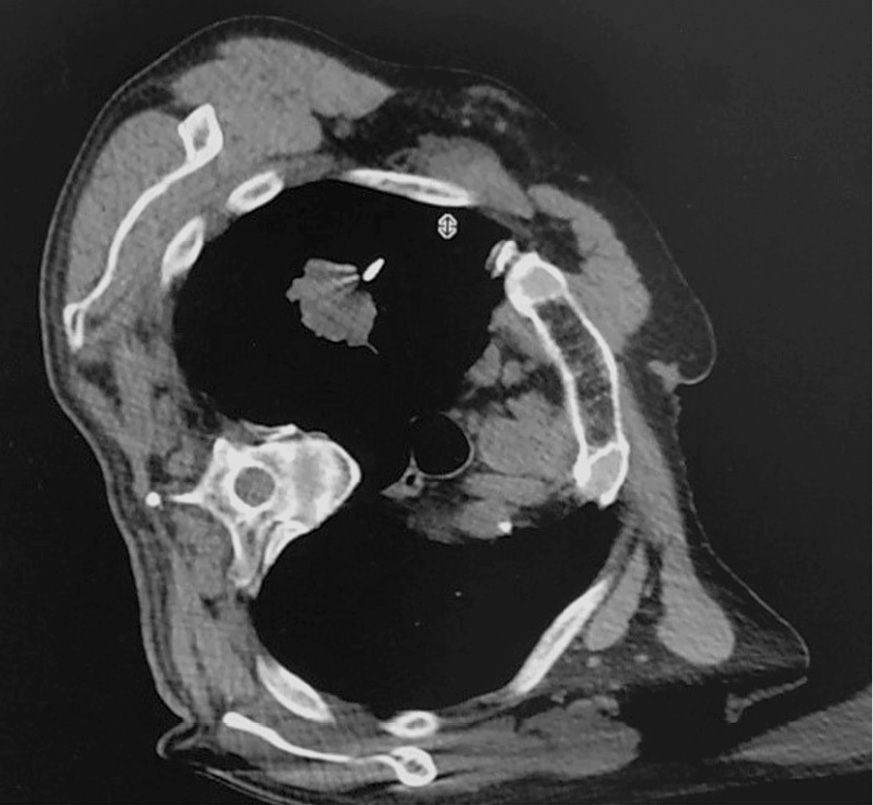

По предварительно полученным данным КТ органов грудной клетки выявлен наиболее короткий и безопасный путь трансторакальной трепанобиопсии. За 30 мин до манипуляции выполнялась премедикация. После этого произведена разметка точки вкола на коже с использованием рентгеноконтрастной (R) метки. Дальнейшее сканирование проводилось с целью контроля правильности установки R-метки, а также определялось расстояние от кожи до опухоли и направление коаксиальной системы (рис. 2).

Рис. 2. Компьютерная томограмма больного В. Установлена R-метка на коже.